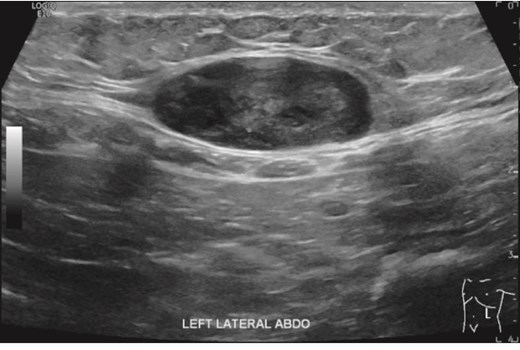

However, 3.5 years after discontinuing imatinib, the patient identified a left upper quadrant subcutaneous mass at age 77. An abdominal ultrasound demonstrated a 16 mm hypoechoic lesion (Fig. 2). A subsequent biopsy confirmed metastatic GIST, again positive for C-Kit and CD34, negative for S100 and SMA, with a mitotic rate of 4 per 50 HPF. Initially suspected to represent a port-site metastasis, operative findings revealed a primary subcutaneous lesion, indicating haematogenous spread. The mass was fully excised and imatinib 400 mg daily was recommenced for a further 4 years, during which no recurrence occurred.

Abdominal US showed a well-defined soft tissue mass attached to the left inferior aspect of the rectus muscle.